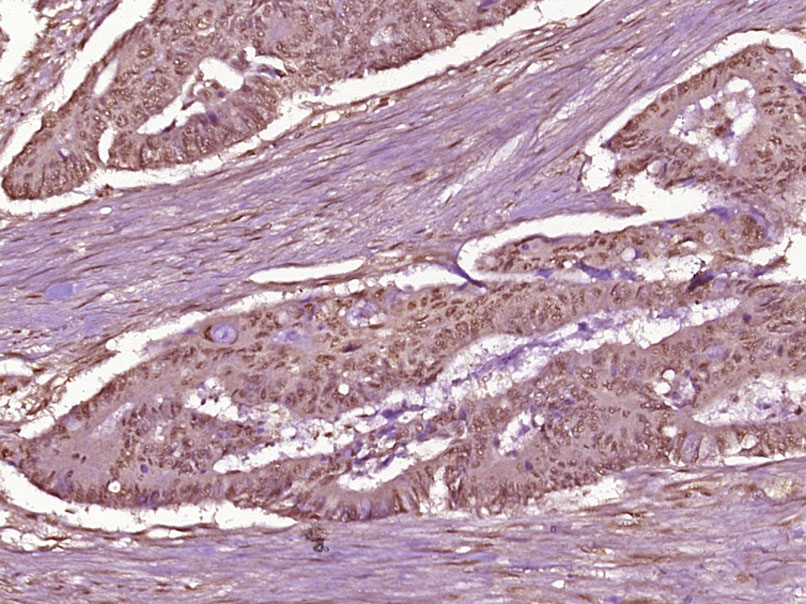

| IHC-P | Human, Rat | Mouse, Pig, Cow, Dog | 1:100-500 |